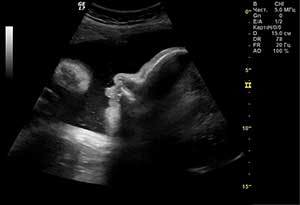

moya istoriya beremennosti 5Август: Третий скрининг и с чем его едят

Количество тестов за этот месяц: много

Количество врачей: 6

Сколько в среднем была в очереди: 30 минут

Заплатила в кассу: 1500 манат

Количество УЗИ: 2

Август – это месяц 32-36 недели беременности.